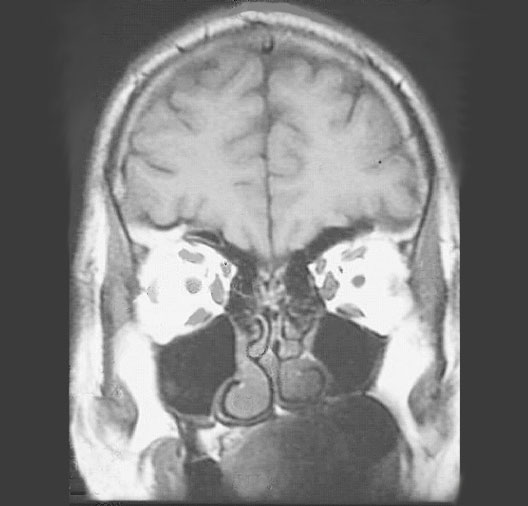

Head MRI Coronal Section

Roll mouse over image to display labels.

1. Superior Oblique muscle

2. Superior Rectus muscle

3. Medial Rectus muscle

4. Lateral Rectus muscle

5. Inferior Oblique muscle

6. Ramus of Mandible

7. Maxillary Sinus

8. Brain

9. Ethmoid Air Sinus

10. Temporalis Muscle

11. Optic Nerve

12. Middle Concha

13. Inferior Concha

14. Tongue